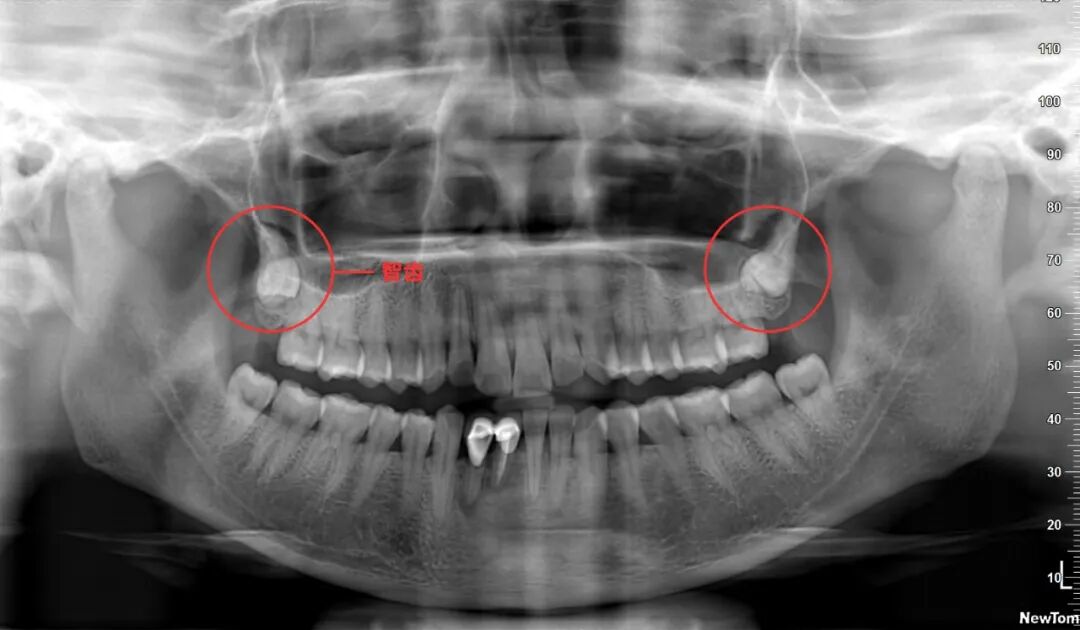

比如这张全景片,全口牙齿一般有 28-32颗,多出来的4颗就是智齿,智齿是从中间的牙齿往后数的第8颗,如果上下左右都有第8颗,那就是长了4颗智齿。